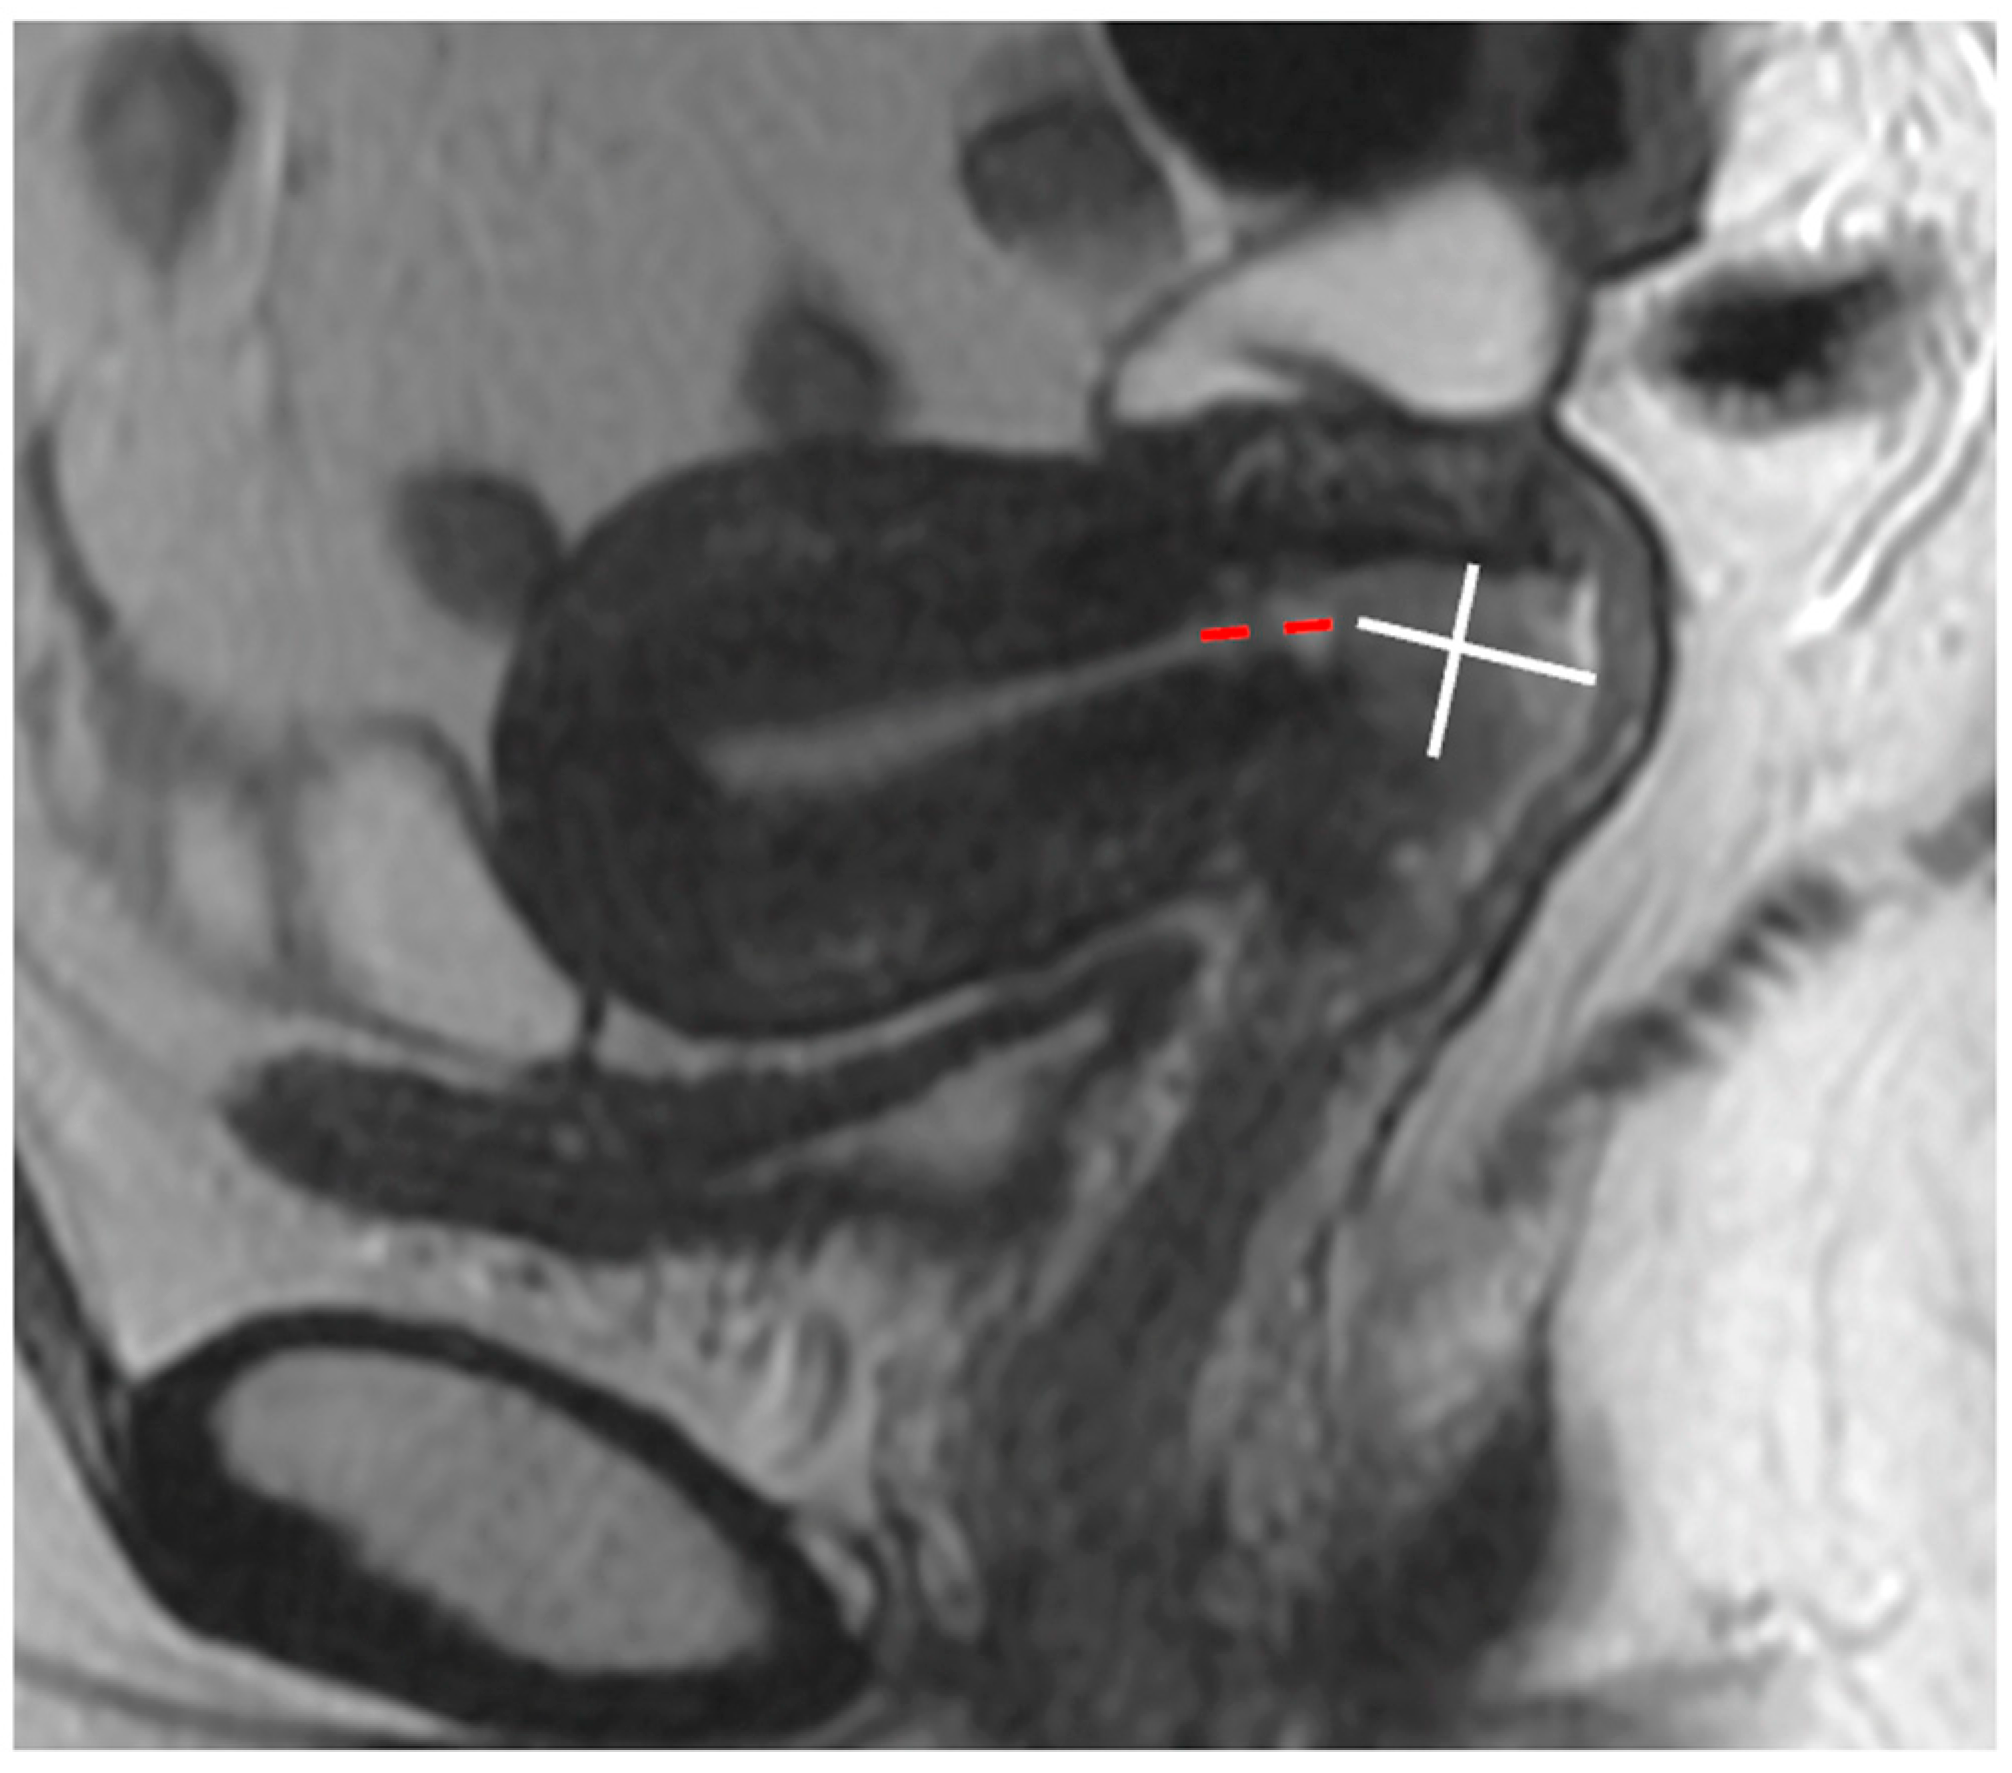

5. FIGO Stage II

- Salvo, G.; Odetto, D.; Saez Perrotta, M.C.; Noll, F.; Perrotta, M.; Pareja, R.; Wernicke, A.; Ramirez, P.T. Measurement of tumor size in early cervical cancer: An ever-evolving paradigm. Int. J. Gynecol. Cancer 2020, 30, 1215–1223. [Google Scholar] [CrossRef] [PubMed]

- Kido, A.; Nakamoto, Y. Implications of the new FIGO staging and the role of imaging in cervical cancer. Br. J. Radiol. 2021, 94, 20201342. [Google Scholar] [CrossRef] [PubMed]

- Young, P.; Daniel, B.; Sommer, G.; Kim, B.; Herfkens, R. Intravaginal gel for staging of female pelvic cancers--preliminary report of safety, distention, and gel-mucosal contrast during magnetic resonance examination. J Comput. Assist. Tomogr. 2012, 36, 253–256. [Google Scholar] [CrossRef] [PubMed]

| Small FOV Sagittal T2WI | Accurate tumour size, local staging (e.g., vaginal, bladder, rectal invasion) |

| Small FOV Axial oblique T2WI | Local staging, parametrial and pelvic sidewall involvement |